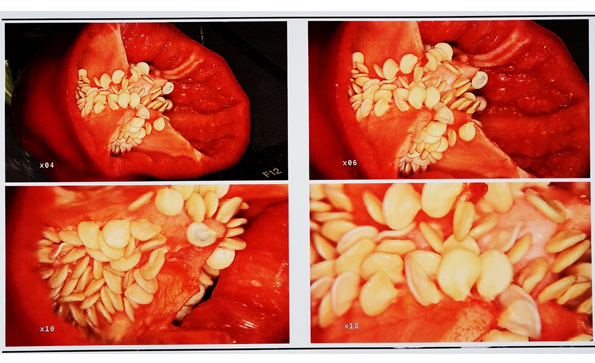

電子陰道鏡放大倍率是多少?